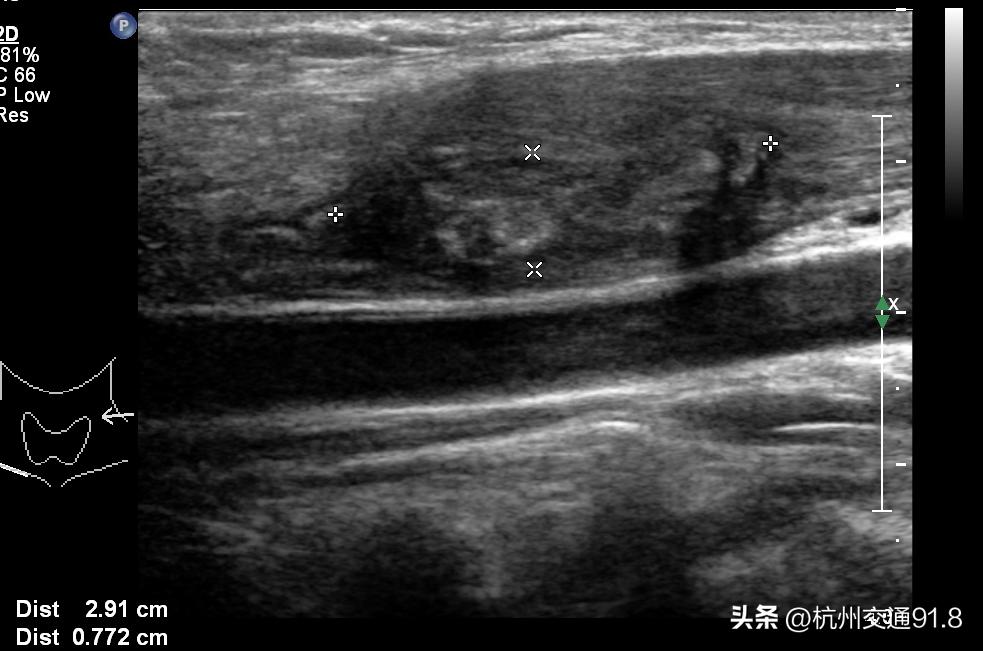

当天晚上小李烧就退了,第二天起来脖子变瘦了,慢慢的牙齿、颈部也都不怎么痛了。半个月后复查,小李颈部的脓包缩小到了2-3cm,恢复得非常快。

术后一周复查 脓包明显缩小